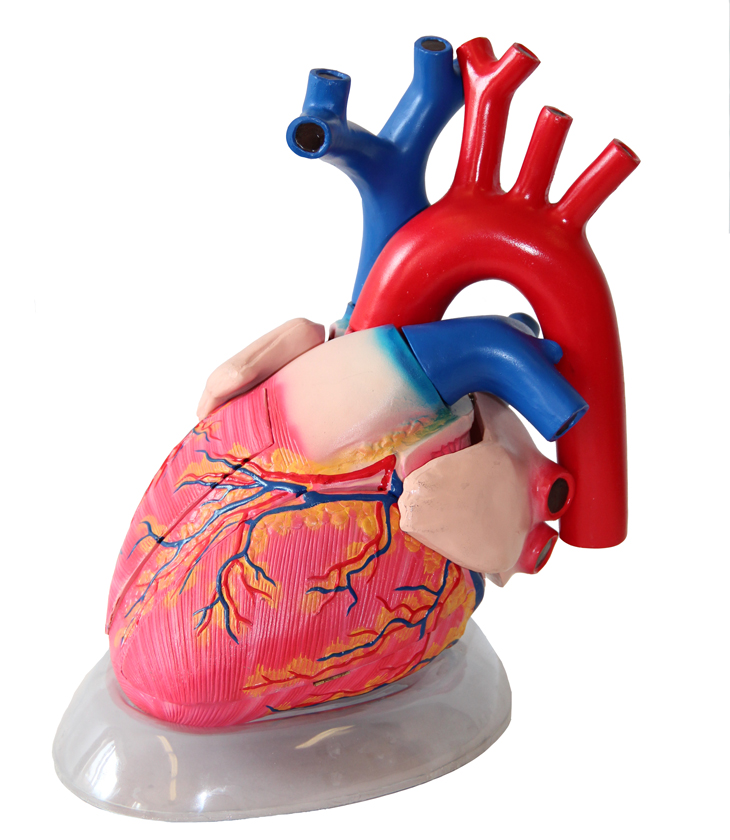

Фотографии и 3D-модели анатомии сердца человека